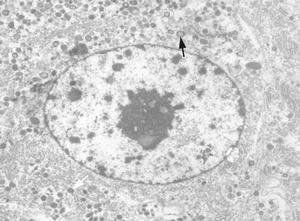

嗜鉻細胞瘤在高血壓病人中患病率為0.05%~0.2%,發病高峰為20~50歲。嗜鉻細胞瘤位於腎上腺者占80%~90%,且多為一側性;腎上腺外的瘤主要位於腹膜外、腹主動脈旁。多良性,惡性者占10%。與大部分腫瘤一樣,散髮型嗜鉻細胞瘤的病因仍不清楚。家族型嗜鉻細胞瘤則與遺傳有關。病理改變